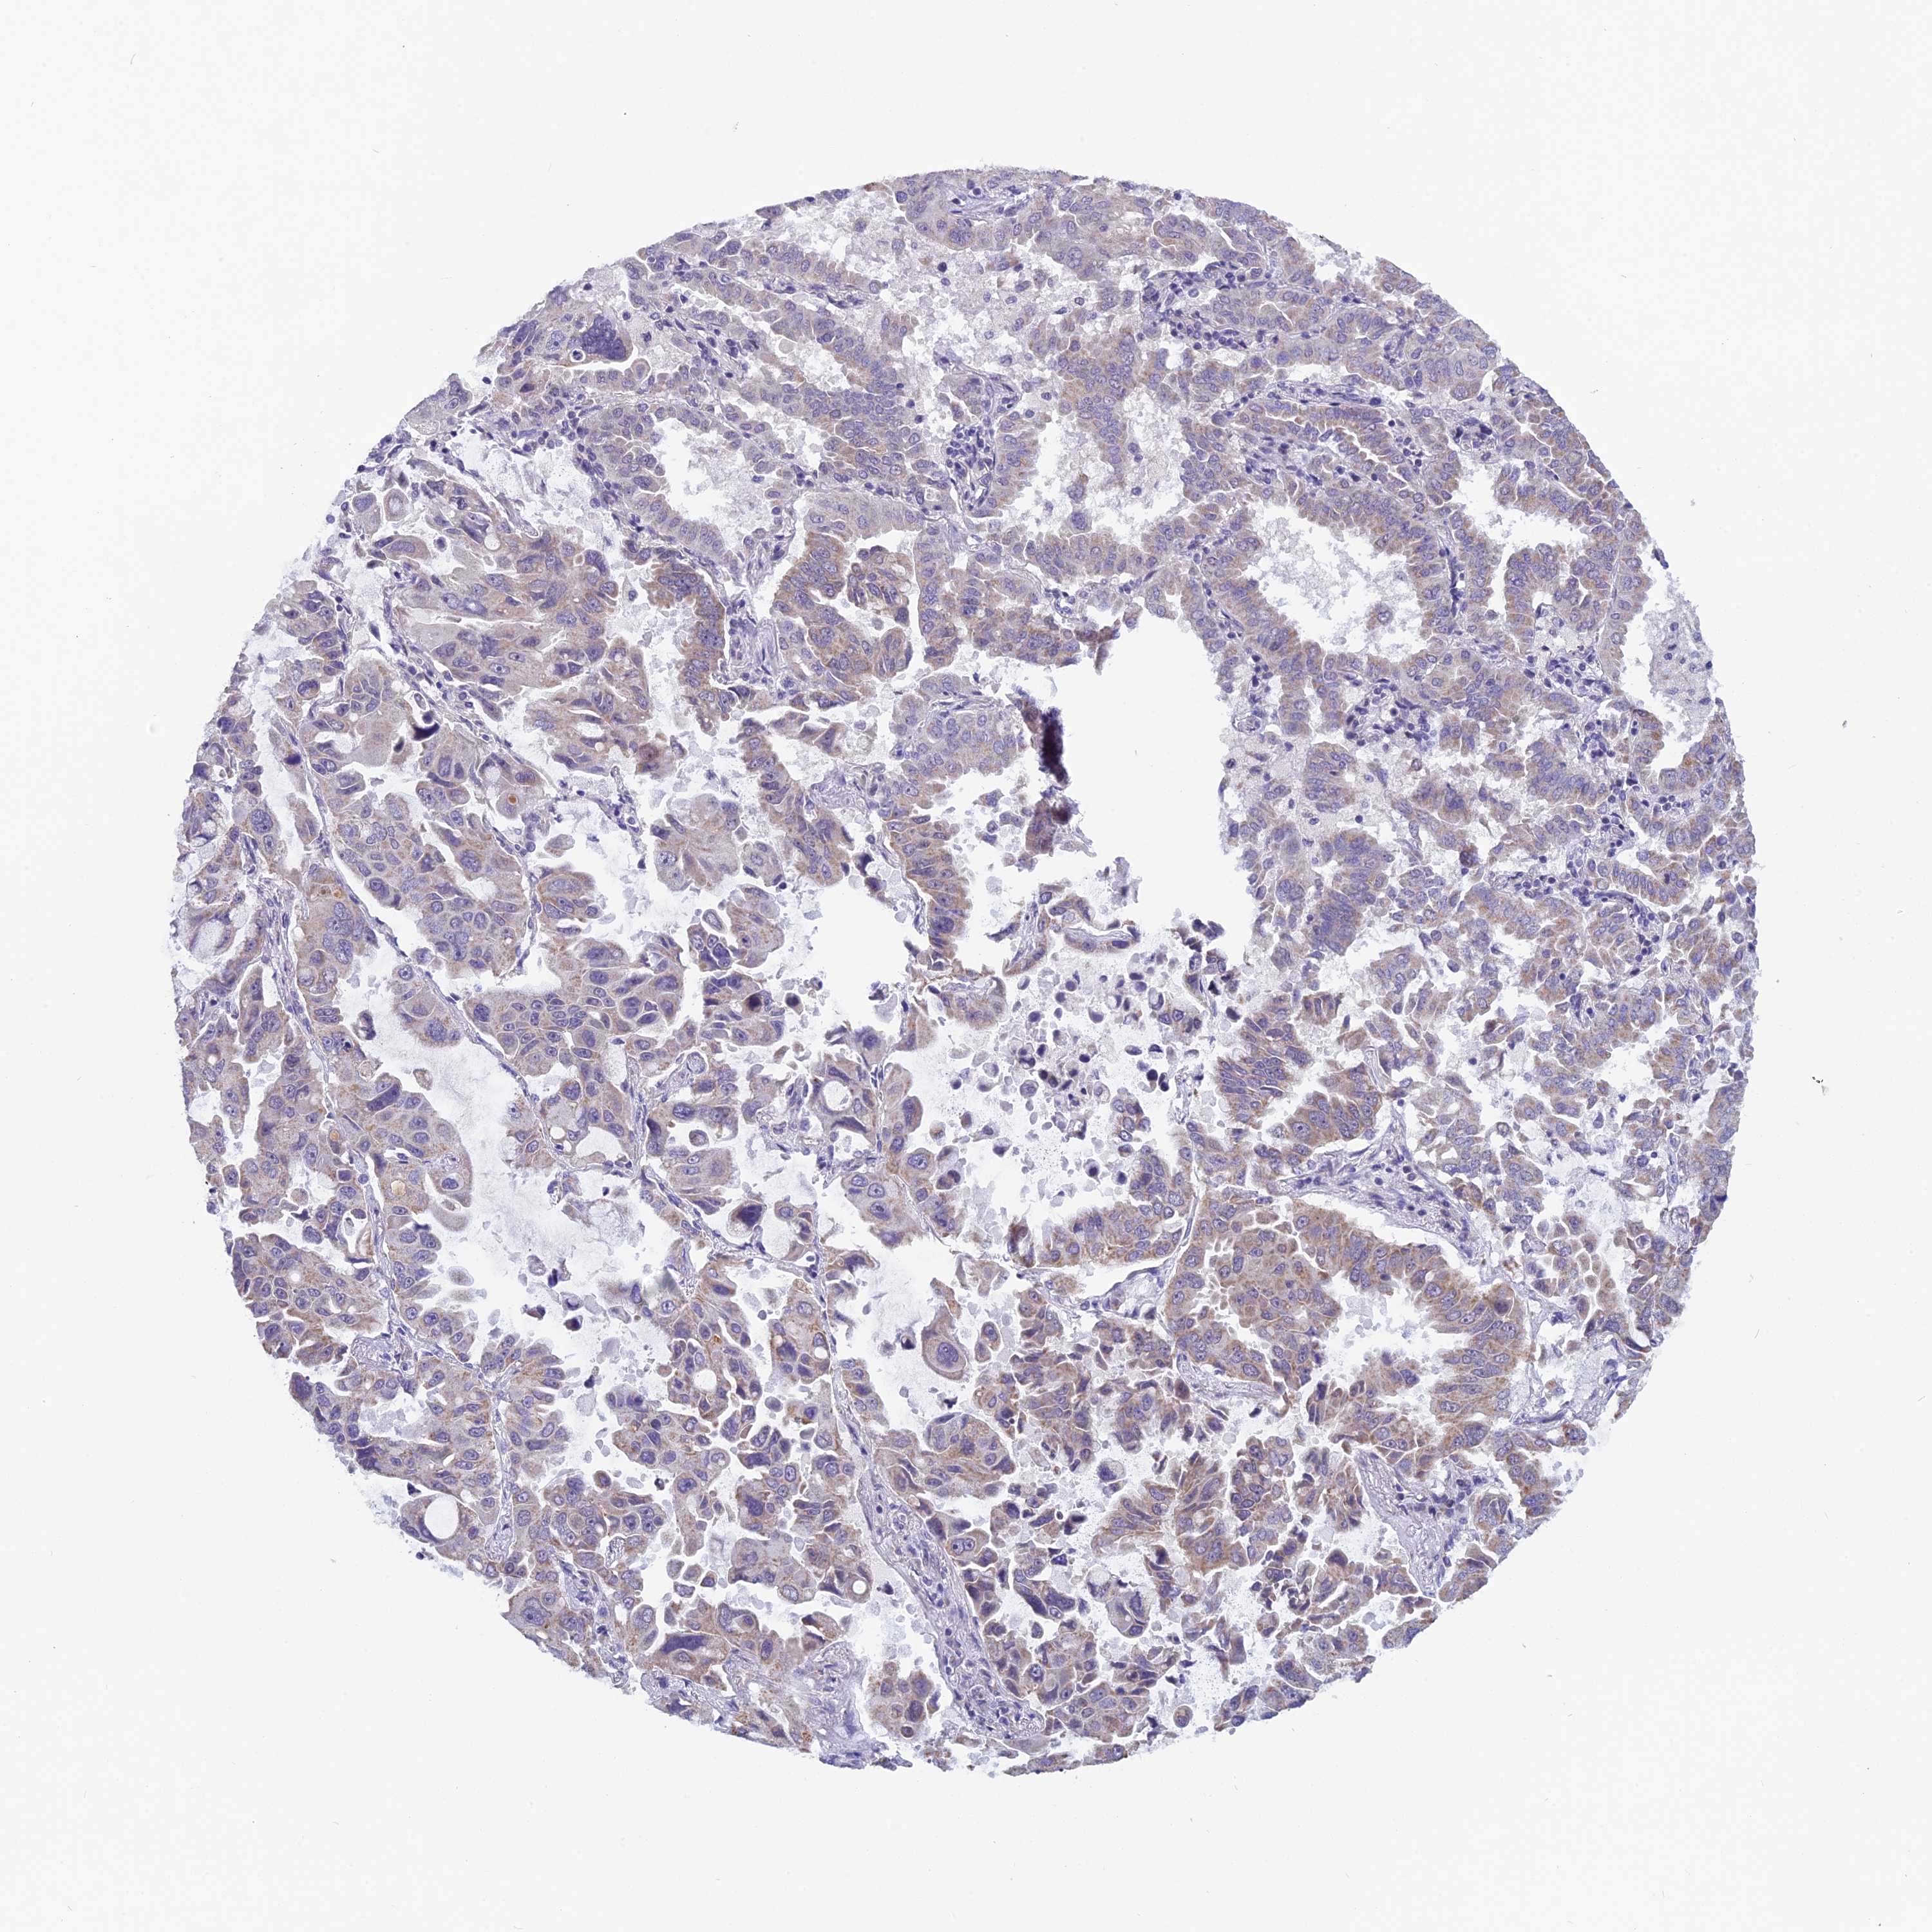

LUNG ADENOCARCINOMA (TCGA) - Interactive survival scatter ploti

The Survival Scatter plot shows the clinical status (i.e. dead or alive) for all individuals in the patient cohort, based on the same data that underlies the corresponding Kaplan-Meier plots. Patients that are alive at last time for follow-up are shown in blue and patients who have died during the study are shown in red.

The x-axis shows the expression levels (FPKM) of the investigated gene in the tumor tissue at the time of diagnosis. The y-axis shows the follow-up time after diagnosis (years). Both axes are complimented with kernel density curves demonstrating the data density over the axes. The top density plot shows the expression levels (FPKM) distribution among dead (red) and alive patients (blue). The right density plot shows the data density of the survived years of dead patients with high and low expression levels respectively, stratified using the cutoff indicated by the vertical dashed line through the Survival Scatter plot. This cutoff is automatically defined based on the FPKM cutoff that minimizes the p-score. The cutoff can be changed by dragging the vertical line or by entering a cutoff value in the square labeled "Current cut-off".

Under the Survival Scatter plot the p-score landscape (black curve; left axis) is shown together with dead median separation (red curve; right axis). Dead median separation is the difference in median mRNA expression between patients who have died with high and low expression, respectively. It is calculated as follows: median FPKM expression of dead patients with high expression - median FPKM expression of dead patients with low expression. This is intended to aid the user in visually exploring custom cutoffs and the associated p-scores and dead median separation.

Individual patient data is displayed and can be filtered by clicking on one or more of the category buttons on the top of the page. Categories describing expression level and patient information include: high, low, alive, dead, female, male and tumor stages. The scale of the x-axis can be toggled between linear and log-scale by clicking on the "x log" button. Mouse-over function shows TCGA ID, patient information and mRNA expression (FPKM) for each patient.

& Survival analysisi

Kaplan-Meier plots summarize results from analysis of correlation between mRNA expression level and patient survival. Patients were divided based on level of expression into one of the two groups "low" (under cut off) or "high" (over cut off). X-axis shows time for survival (years) and y-axis shows the probability of survival, where 1.0 corresponds to 100 percent.

ZNF317 is not prognostic in Lung Adenocarcinoma (TCGA)

Best expression cut offi

Based on the FPKM value of each gene, patients were classified into two groups and association between prognosis (survival) and gene expression (FPKM) was examined. The best expression cut-off refers the FPKM value that yields maximal difference with regard to survival between the two groups at the lowest log-rank P-value. Best expression cut-off was selected based on survival analysis .

When clicking on this number, the vertical dashed line indicating cut-off, the interactive survival plot, and the Kaplan-Meier curve will be adjusted to show results based on the best expression cut-off.

: 16.09

P scorei

Log-rank P value for Kaplan-Meier plot showing results from analysis of correlation between mRNA expression level and patient survival.

N/A

TCGA RNA samplesi

RNA-seq data is reported as average FPKM (number Fragments Per Kilobase of exon per Million reads), generated by the The Cancer Genome Atlas (TCGA) .

Normal distribution across the dataset is visualized with box plots, shown as median and 25th and 75th percentiles. Points are displayed as outliers if they are above or below 1.5 times the interquartile range. FPKM values of the individual samples are presented next to the box plot.

Average pTPM 12.9

Number of samples 497